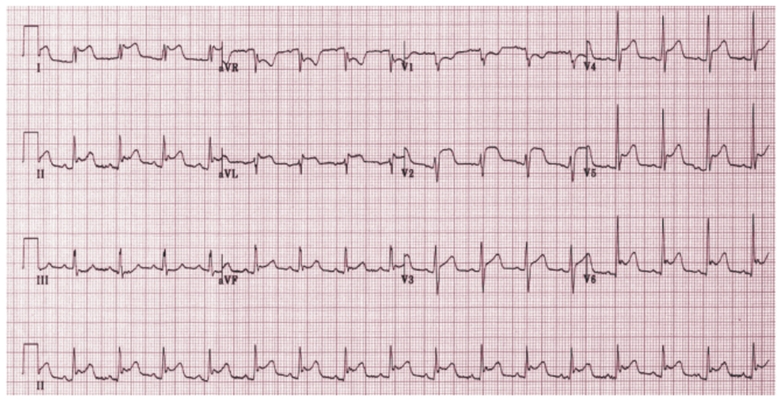

預激綜合症圖片

預激綜合徵心電圖 (79)

預激綜合徵心電圖 (8)

預激綜合徵心電圖 (80)

預激綜合徵心電圖 (81)

A:預激綜合徵典型的心電圖表現是竇性心搏的PR間期縮短,短於0.12s,而且導聯的QRS波群時間超過0.12s。QRS波群起始部分會有粗鈍,終末部分正常,甚至會導致ST-T波型呈現繼發性的改變,甚至於QRS波群主波方向相反。預激綜合徵是指心房……

A:預激綜合徵是很少見的心律失常,是房室傳導異常的一種類型,提早興奮心室的一部分或全部,引起心室肌提前激動,常合併室上性心動過速。心電圖可見PR間期縮短小於0.12秒;QRS時限延長0.11秒以上;QRS波群起始部粗鈍,繼發性ST-T改變。沒有……